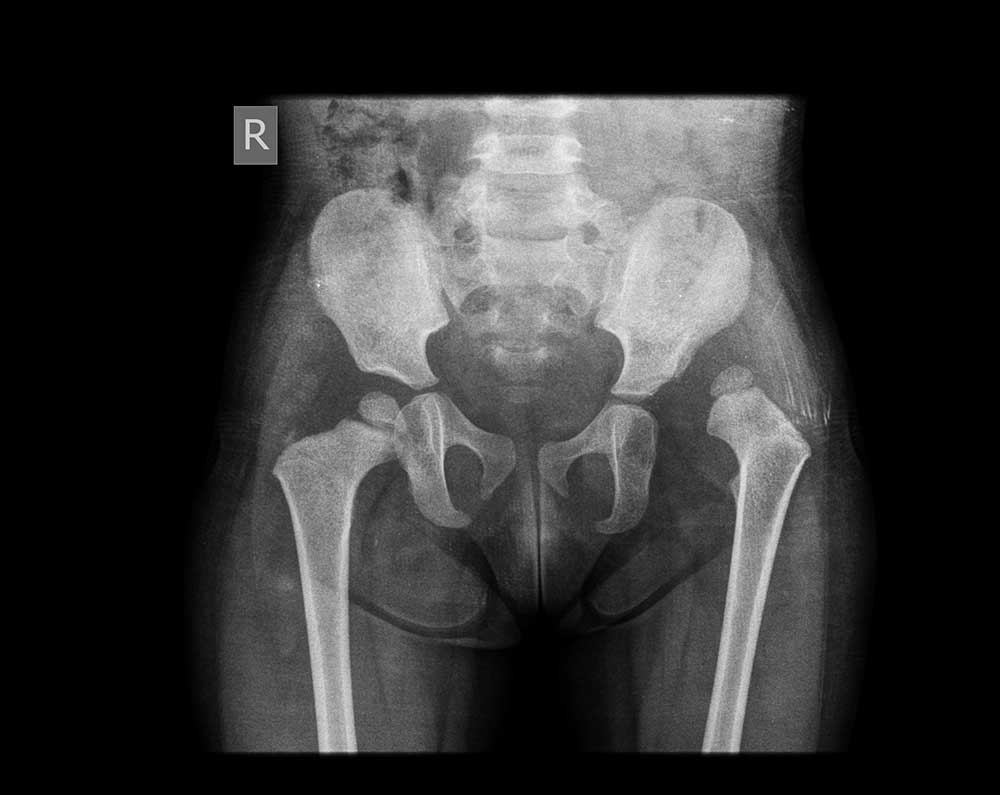

Before surgery

After surgery